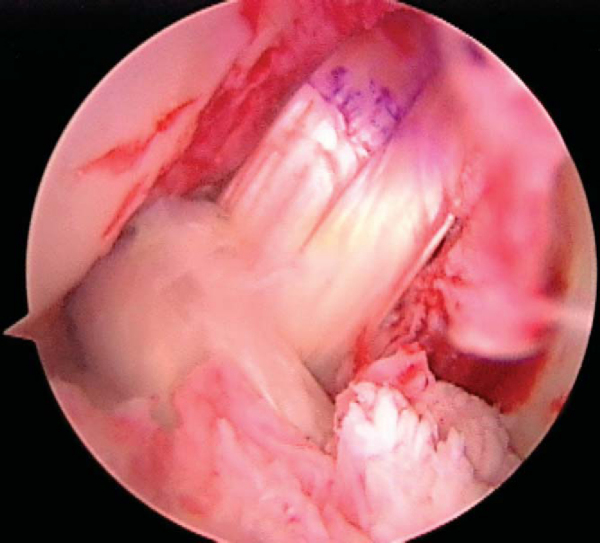

Single-bundle PCL reconstructions are tensioned at 90 degrees of flexion to approximate the anterolateral bundle. An anterior tibial force is applied to reduce the tibia on the femur. The lead sutures of the graft may be tied over a 4.5-mm AO screw and washer, or an interference screw may be used. Tension and tibial fixation of the ACL graft are performed in full extension. Fixation may be achieved with a screw and washer post or an interference screw. The position of the graft and the fixation are checked arthroscopically (

Fig. 71-12

) and clinically.